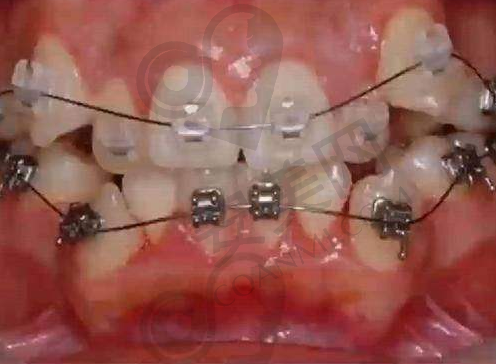

对于金属自锁托槽矫正,刘医生也有着深厚的造诣。金属自锁托槽矫正具有矫正速度快、成效稳定等特点。刘医生在操作过程中,能够精细地将托槽粘贴在牙齿上,并根据患者的牙齿情况调整弓丝的力度,以达到至佳的矫正成效。在治疗过程中,她会定期检查患者的牙齿移动情况,并及时调整矫正方案,确保矫正过程的顺利进行。